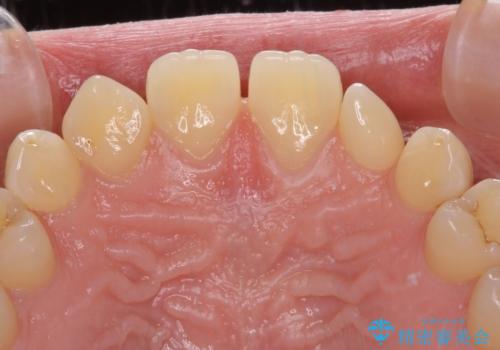

前歯の奇形歯 オールセラミッククラウンによる審美歯科治療

- 前歯の奇形や欠損、乳歯残存などによる審美障害を気にして来院された患者様です。

正中の隙間は矯正治療により閉じ、左右の4歯はオールセラミッククラウンにて補綴することとしました。